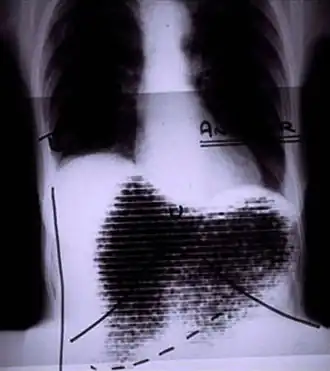

Manual image fusion of x-rayed and rectilinear scanned chest | |

A rectilinear scanner is an imaging device, used to capture emission from radiopharmaceuticals in nuclear medicine. The image is created by physically moving a radiation detector over the surface of a radioactive patient. It has become obsolete in medical imaging, largely replaced by the gamma camera since the late 1960s.[1][2][3]

The patient is administered with a radioactive pharmaceutical agent, such as radio-iodine which will naturally collect in the thyroid. The detector moves in a raster pattern over studied area of the patient, making a constant count rate. A collimator restricts detection to a small area directly below its position so that by the end of the scan emission from the whole study area has been detected. The output method is designed such that positional and detection information is maintained. For example, when using a light source and film the light is moved in tandem with the detector, and the intensity of light produced increases with an increase in activity, producing dark areas on the film.[11][12]